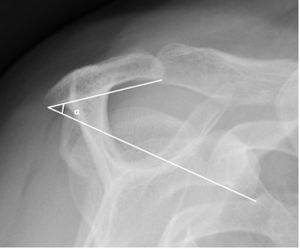

Acromial Slope

Another radiological sign based on the morphology of the acromion is described in 1986 by Aoki et al.[40] It describes the influence of the acromial slope on the lesions of the rotator cuff. Thus, a weak acromial slope measured on the Neer’s incidence is an important factor in the subacromial impingement (Figure). Other studies also confirm this trend.[41][42][33]